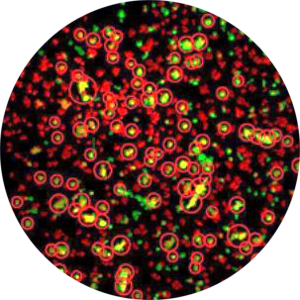

Cell Infection Assay